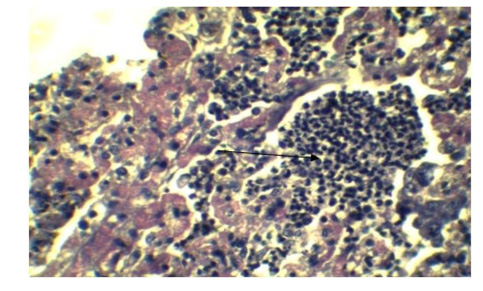

Infiltration of inflammatory cell in Lung parenchyma (Arrow), feature of interstitial pneumonia. (H&E x 40)